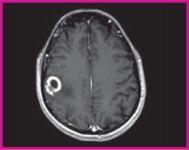

January 24, 2011 – A U.S. Food and Drug Administration’s (FDA) panel voted unanimously last week to recommend the clearance of a magnetic resonance imaging (MRI) contrast agent to detect and visualize areas with disrupted blood brain barrier and/or abnormal vascularity of the central nervous system (CNS). The FDA’s Peripheral and Central Nervous System Drugs Advisory Committee said clinical trial and postmarketing data for a gadobutrol injection, a macrocyclic 1.0 molar gadolinium-based contrast agent (GBCA), support approval of the product. In addition to the vote for approval, committee members concurred in a 15-1 vote that gadobutrol should be labeled without an nephrogenic systemic fibrosis (NSF) contraindication in the at-risk population. NSF is a very rare but serious disease that affects a small percentage of patients with severe renal impairment who undergo contrast-enhanced MRI. All marketed GBCAs have a boxed warning about the potential for NSF in patients with chronic severe kidney disease or acute kidney injury. Gadobutrol is formulated at a 1.0 molar concentration (mol/L), which provides a higher concentration (lower volume) compared to other contrast agents used for CNS imaging. Bayer HealthCare Pharmaceuticals Inc. said it will continue to work with the FDA as it finalizes its review of gadobutrol. "Bayer is pleased that the advisory committee recognized the totality of the clinical and post-marketing data presented today," said Pamela A. Cyrus, M.D., vice president and head of U.S. medical affairs, Bayer HealthCare Pharmaceuticals. "If approved by the FDA, Bayer believes that gadobutrol will provide healthcare providers with an additional new option for CNS imaging in the United States." Data presented at the advisory committee meeting included results from two adequate and well-controlled phase 3 studies that confirmed the efficacy and safety of gadobutrol injection in contrast-enhanced MRI of the CNS. Prospectively defined primary and secondary endpoints were met in the two studies. The first phase 3 study compared the efficacy of combined gadobutrol-enhanced images plus unenhanced images to unenhanced images alone. The second phase 3 study used a crossover design with an active control, gadoteridol, to also compare the efficacy of the combined gadobutrol-enhanced plus unenhanced images to unenhanced images alone, as well as to confirm noninferiority of combined gadobutrol imaging versus combined gadoteridol imaging. The results of the first phase 3 study showed that gadobutrol-enhanced images compared to unenhanced images were superior in diagnostic performance and superior for the visualization variables, contrast enhancement, border delineation, and internal morphology. The results for comparison of unenhanced images compared to gadobutrol-enhanced images were consistent across both Phase 3 trials. In the second Phase 3 study comparing gadobutrol-enhanced images to images enhanced with the approved contrast agent gadoteridol, gadobutrol was confirmed to be non-inferior to gadoteridol with respect to visualization variables, contrast enhancement, border delineation and internal morphology, as well as the number of lesions detected. The most common adverse drug reactions observed in phase 2-4 trials for gadobutrol were generally consistent with those of other gadolinium based contrast agents. Across the studies (n=4,549), the most common adverse events associated with gadobutrol were: headache (1.5%), nausea (1.2%), injection site reactions (0.6%), dysgeusia (0.5%), feeling hot (0.5%), dizziness (0.4%), vomiting (0.4%), rash (0.3%), pruritis (0.2%), erythema (0.2%), dyspnea (0.2%), parasthesia (0.1%). During the entire clinical development program of gadobutrol, only isolated reports of serious adverse events were recorded. Overall, serious AEs (including fatal) were observed in 17 (0.4%) of 4,549 patients. One of the 17 serious AEs reported in the gadobutrol group was considered drug-related by the investigator (crystals in urine one day after injection). The New Drug Application (NDA) for gadobutrol was submitted to the FDA on May 14, 2010. The advisory committee's recommendations are not binding, but FDA reviewers will consider the panel's recommendation in its final assessment of the NDA. For more information: www.bayer.com